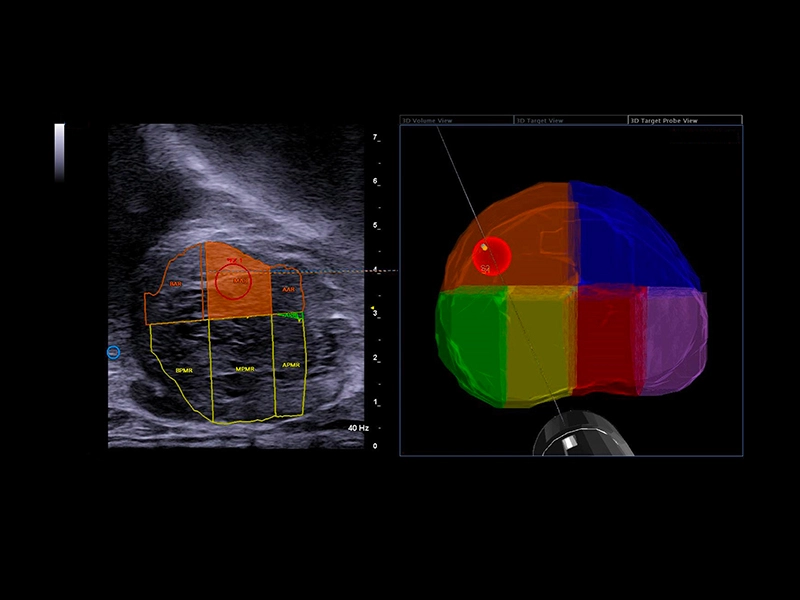

MyLab™E80 - Urofusion - Systematic Biopsy Guide

MyLab™E80 - Urofusion - Systematic Biopsy Guide